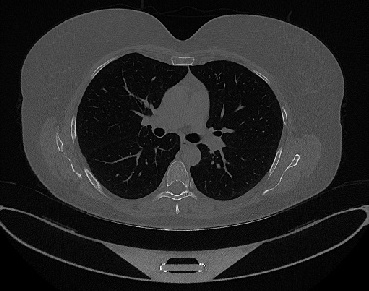

It should be mentioned that for explainability purposes [7, 8, 9], an anchor set was generated for the COV19-CT-DB database [5]. This included 11 anchors, each representing a respective 3-D CT scan obtained through an appropriate clustering procedure. Figure 2 shows a series of slices from a COVID-19 case, whereas Figure 3 shows a series of slices from a non COVID-19 case.